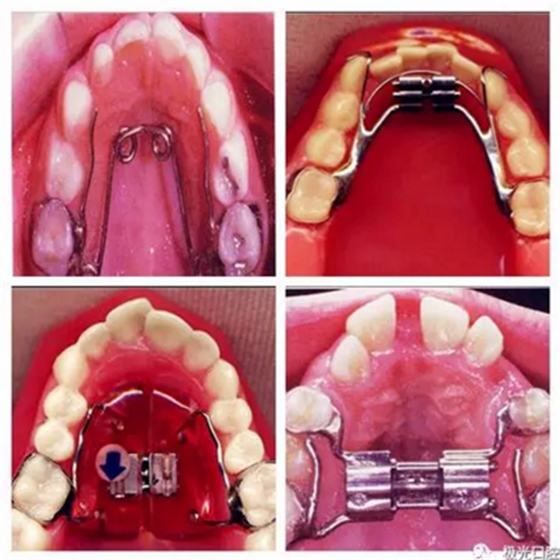

三、擴(kuò)弓器

很多牙列不齊常伴隨牙弓過窄,所以擴(kuò)弓器是正畸醫(yī)生的好伙伴,它可以以多種形態(tài)和您見面。以下是幾種常見的擴(kuò)弓器,想想您的口腔內(nèi)將安放這些東西……